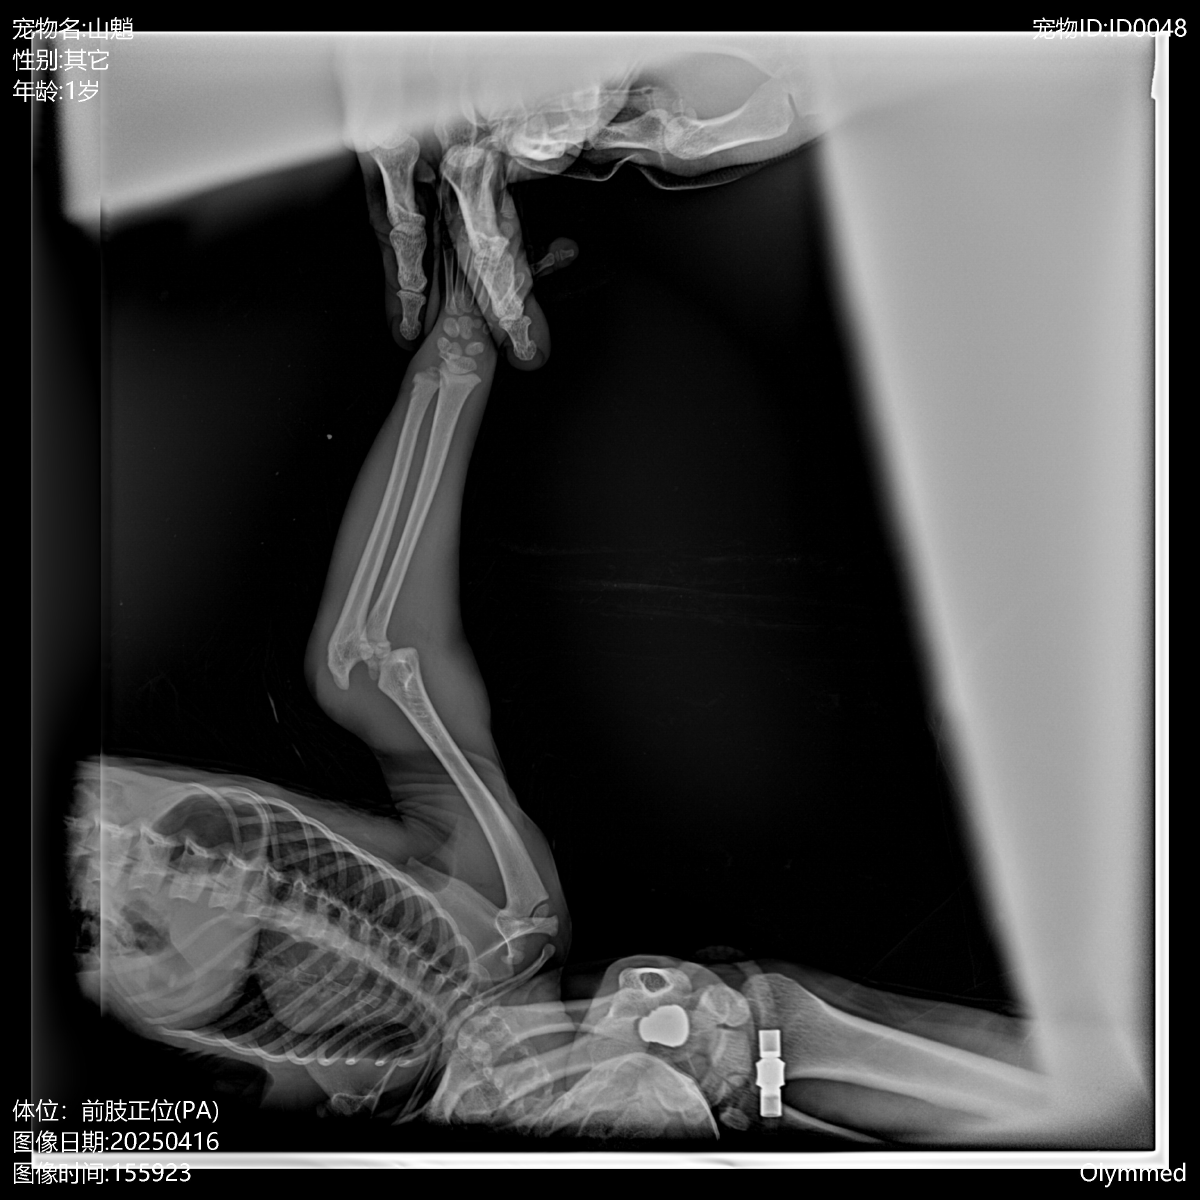

山魈骨折后的紧急治疗

一只8月龄山魈左前肢肘部确诊为生长板骨折,经评估必须进行手术。兽医团队为其成功施行了克氏针内固定术。术后恢复顺利,患肢在短期内即恢复了良好的抓握能力与关节活动度,现已行动自如。